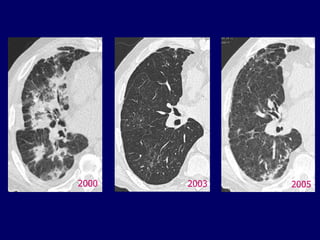

2000

2003

2005

Chest 2003;124:1185